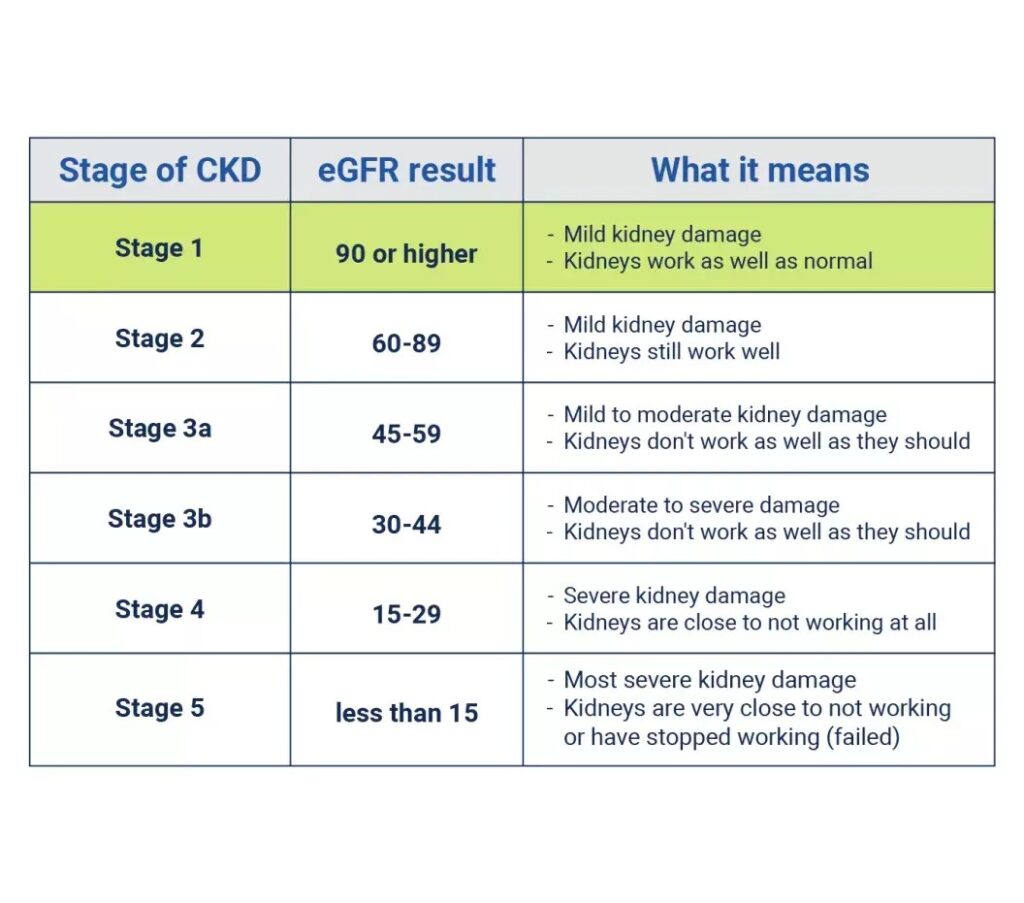

වකුගඩු රෝගී වීමේ ප්රධාන ලක්ෂණයක් වන්නේ වකුගඩුවල වකුගඩුවලින් රුධිරය පෙරීමේ අනුපාතය, Glomerular Filtration Rate (GFR) අඩු වීමයි.මෙම අනුපාතයෙන් තමයි අපේ වකුගඩු කෙතරම් කාර්යක්ෂමතාවයකින් රුධිරය පෙරීමකට ලක් කරනවද කියල කියවෙන්නේ. සාමාන්ය නිරෝගී පුද්ගලයෙකුගේ මෙම GFR අගය 90ක් හෝ ඊට වැඩි අගයක් ගන්නවා. වකුගඩු රෝගය ක්රමක්රමයෙන් වැඩිවීමත් සමග මෙම අගය අඩු වීම සිදුවෙනවා.එයින් කියවෙන්නේ වකුගඩුවල ක්රියාකාරී තත්වයේ පවතින වෘක්කානු අඩුවෙමින් වකුගඩුවල පෙරීමේ හැකියාව අඩුවෙමින් පවතින බවයි.

ඉතින් මේකට තමයි වකුගඩු රෝගය කියල කියන්නේ. වෛද්යවිද්යාවේදී වකුගඩු රෝගයේ අවධීන් කිහිපයක් හදුනාගෙන ඒ ඒ අවධීන් වලදි වකුගඩු වල ක්රියාකාරීත්වයේ මට්ටම් ගැනත් සඳහන් කර තිබෙනවා. ඒ අවදීන් ගැන අපි තවත් ලිපියකින් කතා කතා කරමු